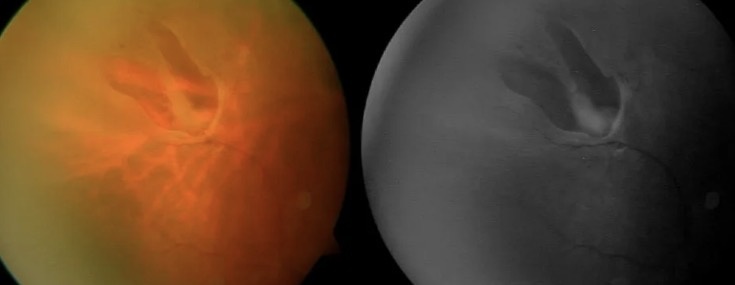

Клапанный разрыв на сетчатке (horseshoe tear) — это U-образный дефект сетчатки, где flap ткани отрывается, часто предшествуя отслойке.

**Диагностика.** Фундускопия с расширением зрачка, ОКТ для детализации.